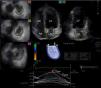

Images from three-dimensional full-volume dataset showing left atrium: apical 4-chamber (A) and 2-chamber views (B) and short-axis views at basal (C3), mid- (C5) and superior (C7) left atrial level are demonstrated together with left atrial volumetric data and a three-dimensional cast of the left atrium. Time-segmental strain curves of all 16 left atrial segments and global left atrial volume changes throughout the cardiac cycle are also presented. White arrow: peak strain. LA: left atrium; LV: left ventricle; RA: right atrium; RV: right ventricle; Vmax, Vmin and VpreA: maximum and minimum left atrial volumes and left atrial volume before atrial contraction, respectively.

From the same 3D echocardiographic datasets, time curves of one-directional radial (RS), longitudinal (LS) and circumferential (CS) strains were also generated for each segment using the 16-segment model obtained for the left ventricle (Figure 1).10–12 Moreover, due to the ability of 3DSTE to calculate complex strains, area strain (ratio of endocardial area change during the cardiac cycle) and 3D strain (strain in the wall thickening direction, combination of one-directional strains) were also measured. On each time-segmental strain curve, peak strains representing characteristics of the reservoir phase of LA function were measured. Global strains were calculated by the software considering the whole LA, while mean segmental strains were obtained as the mean of strains of 16 segments. The software calculated these parameters automatically.